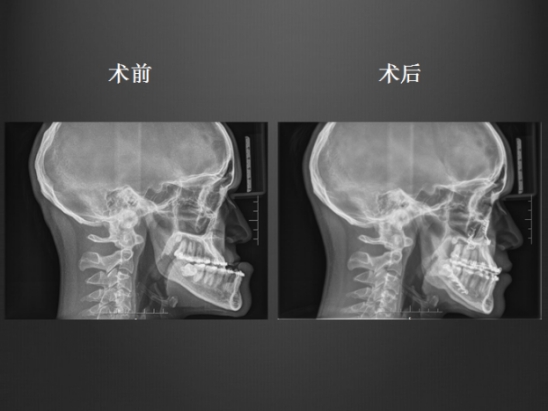

从事口腔颌面外科临床工作10余年,专业特长主要有面部下颌骨偏斜外科治疗,下颌骨前突(地包天)、下颌骨后缩(小下颌)、面部骨骼牵引延长或牙槽骨增高、下颌角宽大(国字脸)的外科治疗;颞下颌关节疾病和关节强直(张口受限);微创拔牙术,如各类复杂阻生牙、埋伏智齿及复杂牙的微创拔除;大型颌骨囊肿的功能外科治疗;牙槽突修整术、牙槽突裂植骨术;口腔颌面部良恶性肿瘤的综合治疗等。

王冬香所在的颅颌面畸形正颌外科团队,是贵州省首家开展正颌外科手术的团队,2018年开展数字化外科设计方案,采用3D打印模型指导手术,使手术更精准,获得面部外形及功能俱佳的治疗效果,其学科水平处于国内领先。王冬香主持开展的院级新技术新项目3D打印塞治器在大型下颌骨囊肿中的应用,遵循功能外科及微创外科的理念,最大限度的保留颌骨外形,创伤小,并发症少,使患者获得更加简单、微创、舒适、经济、有效的治疗。

正颌外科手术病例